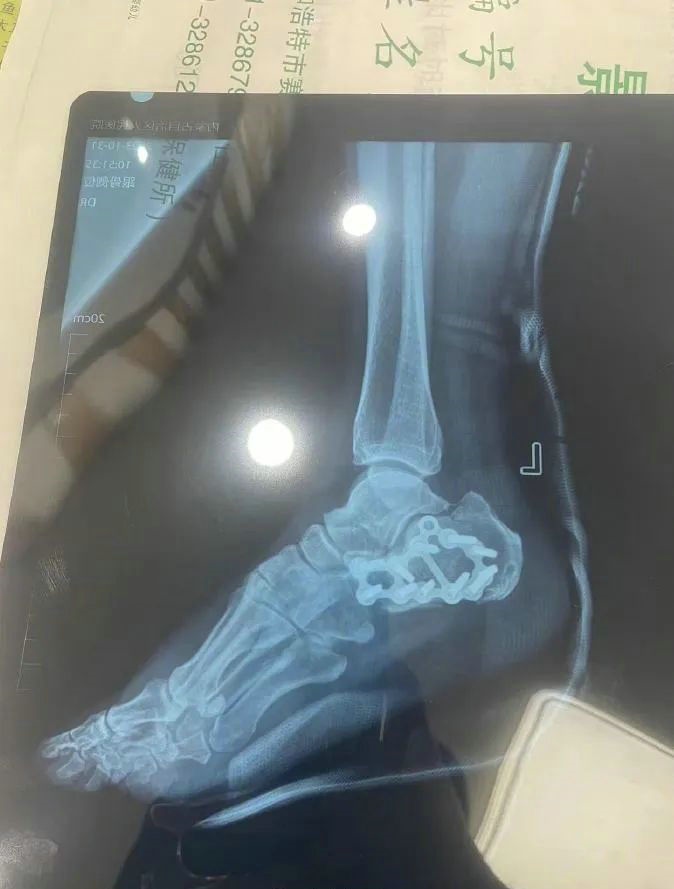

“那時(shí)候我剛工作了兩天,在第三天10月22日下午施工過程中從三層高的鐵架上摔了下來,導(dǎo)致30厘米左右的鋼筋刺穿我的右側(cè)臀部,左腳跟也粉碎性骨折,被送往內(nèi)蒙古自治區(qū)人民醫(yī)院救治,當(dāng)晚做了手術(shù)取出刺在右臀部的鋼筋,10月30日又進(jìn)行了左腳粉碎性骨折手術(shù)?!崩紫壬嬖V記者。

據(jù)雷先生介紹,當(dāng)時(shí)內(nèi)蒙古騰龍建設(shè)工程有限公司許經(jīng)理問過他賠付10萬元能否解決問題,他認(rèn)為這樣不太妥當(dāng)?!耙?yàn)槲业淖竽_骨折還要進(jìn)行二次手術(shù),并且我臀部受傷不能坐著,只能包車回家,會(huì)產(chǎn)生一系列的費(fèi)用?!崩紫壬f?! ?/p>